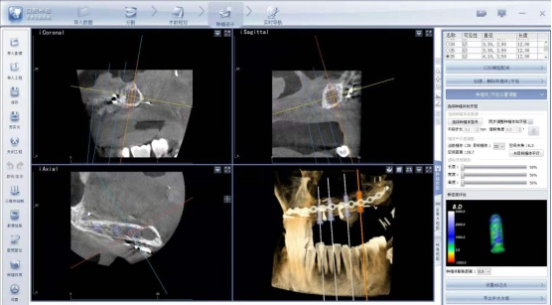

術(shù)中導(dǎo)航屏幕界面